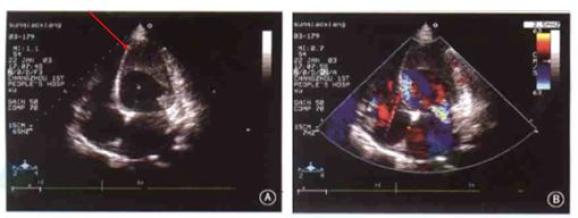

心尖肥厚型心肌病的T波倒置

图7 胸前导联(V4~V6)T波倒置如图7,V4~V6导联出现T波倒置,倒置的T波振幅异常升高,呈TV4> TV5> TV3,T波形态双肢略不对称,基底部变窄。

除此以外,V4~V6导联的R波幅度升高,且RV4> RV5> RV3,此为肥厚心肌除极向量增大的结果。

图8 心尖肥厚型心肌病的心超表现如图8,心脏彩超可见心尖部心肌明显增厚。